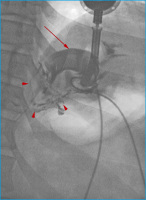

LAGB

Abbildung 4: Lateral exzentrische Pouchdilatation nach LAGB: Das Magenband ist verkippt mit einem Phi-Winkel von > 90°. Kranial des Bandes findet sich ein großer, mit Kontrastmittel gefüllter Pouch (Pfeilspitze), der dem hochgerutschten Magenfundus entspricht. Die Passage durch das Magenband ist erhalten.

Keywords: GastroenterologieLAGBMagenbandPouchdilatationRöntgenbild